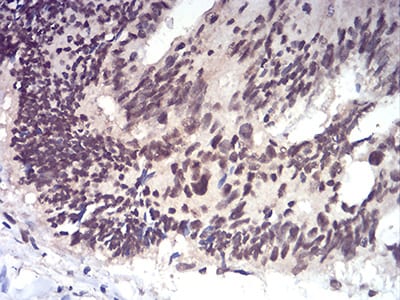

Immunohistochemical analysis of paraffin-embedded human esophageal cancer tissues using RAD50 mouse mAb with DAB staining.

Immunohistochemical analysis of paraffin-embedded human rectum cancer tissues using RAD50 mouse mAb with DAB staining.